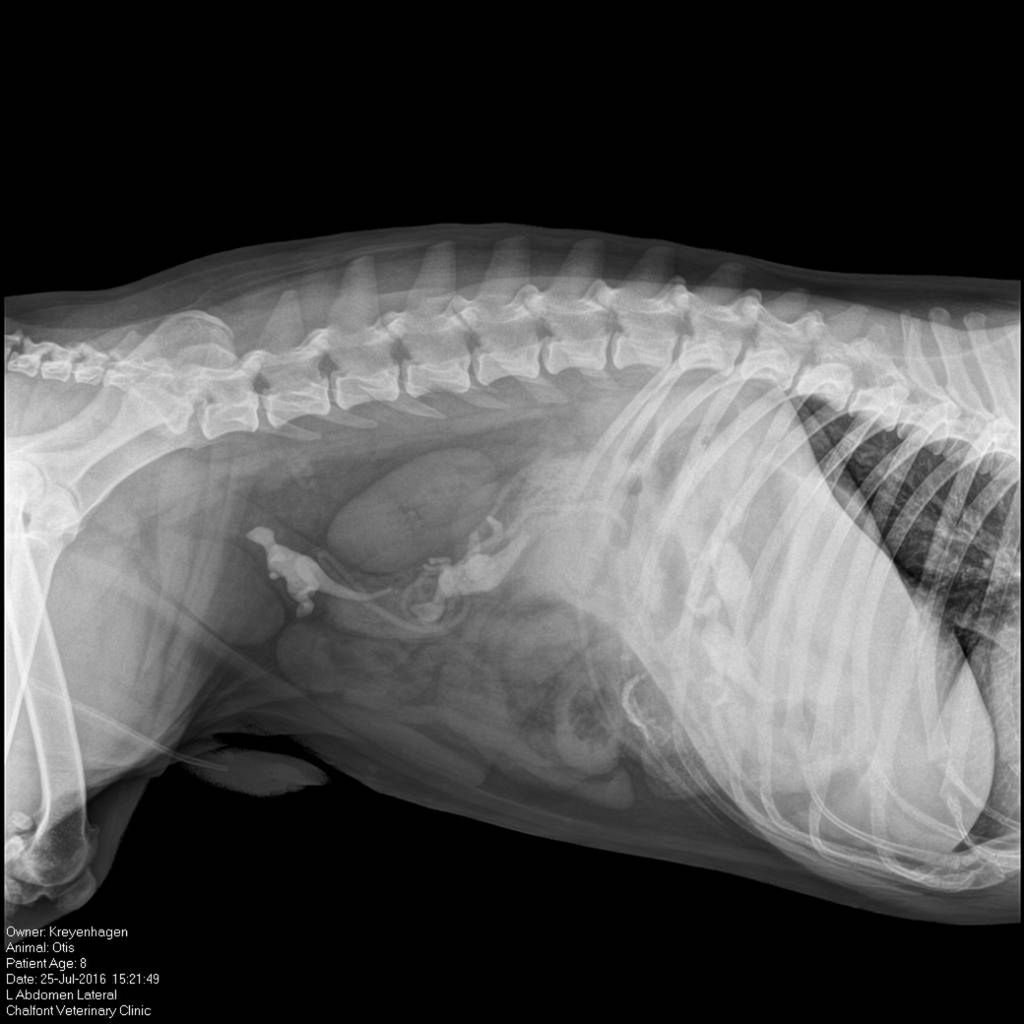

/ 11Dinozaury

Obraz

© Veterinary Practice News / Eileen V. Lindmeier, VMD, of Chalfont Veterinary Clinic LLC in Chalfont, Pa.

8-letni angielski buldog o imieniu Otis niedomagał i tracił na wadze, więc właściciel zabrał go do lecznicy. Po podaniu środka na przeczyszczenie z psa wyskoczyły dwa małe metalowe dinozaury. Prześwietlenie pokazało, że w Otisie zostały jeszcze dwa inne. W czasie operacji wydobyto obie figurki.